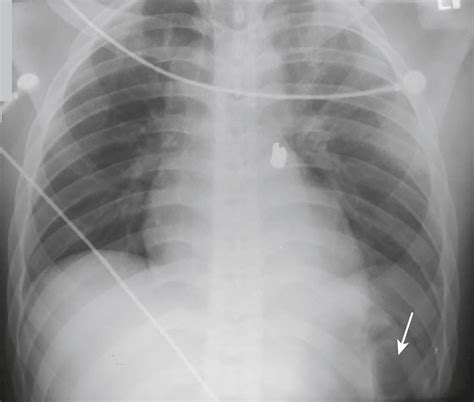

The Deep Sulcus Sign is characterized by an abnormally deep and lucent (dark) costophrenic angle on a supine chest X-ray. Under normal circumstances, the costophrenic angle—the sharp point where the diaphragm meets the ribs—should be relatively shallow. When a pneumothorax occurs in a supine patient, the free air tracks to the most non-dependent part of the pleural space, which, in this position, is the anterior and lateral costophrenic sulcus.

This accumulation of air causes the costophrenic angle to appear hyperlucent and deeper than usual, often extending further inferiorly than the contralateral side. Recognizing this sign is paramount because, in supine radiography, standard signs of pneumothorax—such as the visualization of a visceral pleural line—are frequently absent or obscured, leading to a high rate of missed diagnoses.